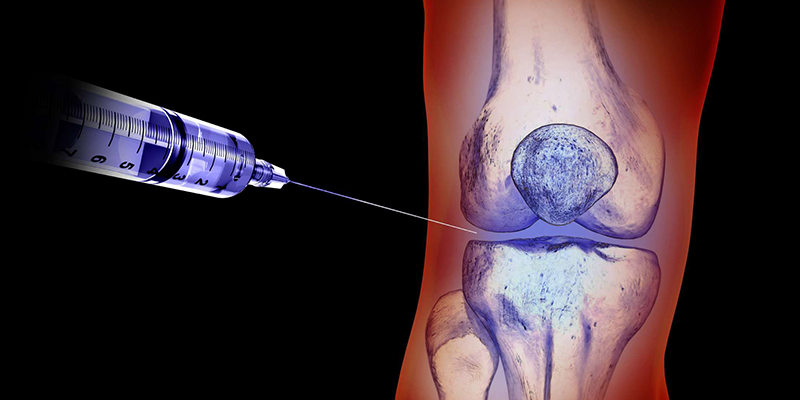

Diz yaralanmalarında enjeksiyon uygulamaları

Diz eklemi: Hasta diz ekstansiyonda olacak şekilde supin pozisyonda yatırılır. Patella sınırları belirlenir ve bir elle medialden laterale doğru itilerek lateral patellofemoral aralık belirginleştirilir. İğne lateralden mediale doğru uygulanır. Solüsyon yavaş bir şekilde enjekte edilir (5).